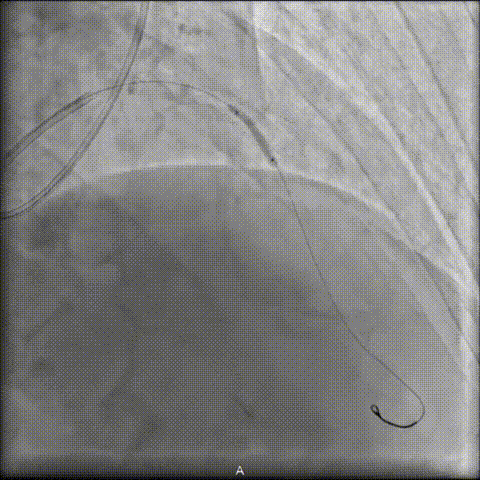

4 前向冲击波导管成功”开路”

经充分评估病情后,陆浩教授将前向冲击波导管作为关键突破策略:导管推送并稳抵病变后,实施“推进式治疗”,经6周期治疗后,术者即感明确的“突破感”,导管随之成功通过钙化病变段。